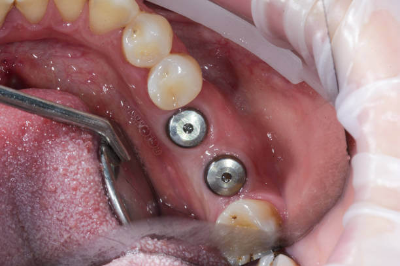

환자분(김ㅇ진님)은 #34 부위에 임플란트 수술을 받으셨습니다. 수술은 약 30분 만에 순조롭게 마쳤습니다.

그날 오후 2시에 수술을 받으신 환자분께 저녁 7시에 전화를 드렸는데, 통증은 거의 없었으나 입술에 지릿지릿한 감각이 남아 있다고 하셨습니다. 이후에도 환자분의 동의를 얻어 2시간마다 새벽까지 상태를 확인했습니다.

새벽 2시까지도 감각 이상이 지속되어, 다음날 아침 첫 진료 시간에 내원하시도록 안내했습니다. 검사 후 픽스처를 2mm 짧은 것으로 교체하는 재수술을 진행했고, 다행히 5시간 만에 입술 감각이 회복되었습니다.